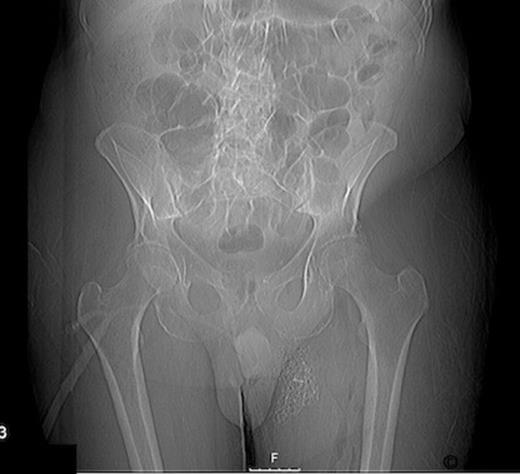

Radiographs confirmed subcutaneous gas associated with the swelling (figure 1). The patient was consented for incision and drainage of the collection, where it was noted that gas bubbles were released on initial stab incision. Copious grey watery fluid was drained from the cavity which appeared to track under the inguinal ligament. Cavity fluid and biopsy specimens were sent for microscopy, culture and sensitivity. The cavity was packed and broad spectrum antibiotics were started following consultation with a microbiologist. A pelvic CT scan with contrast was arranged (figure 2–4), which confirmed a vesicocutaneous fistula.

Figures 2, 3, and 4 are axial, sagittal, and coronal views, respectively, of computed tomography with contrast introduced by urinary catheter. This CT cystogram shows a leak/fistula at the low anterior bladder wall. The fistula has a communication with the pubic symphysis and a collection lies anterior to this. The tract extends distally, communicating with the cavity in the left anteromedial aspect of the thigh.